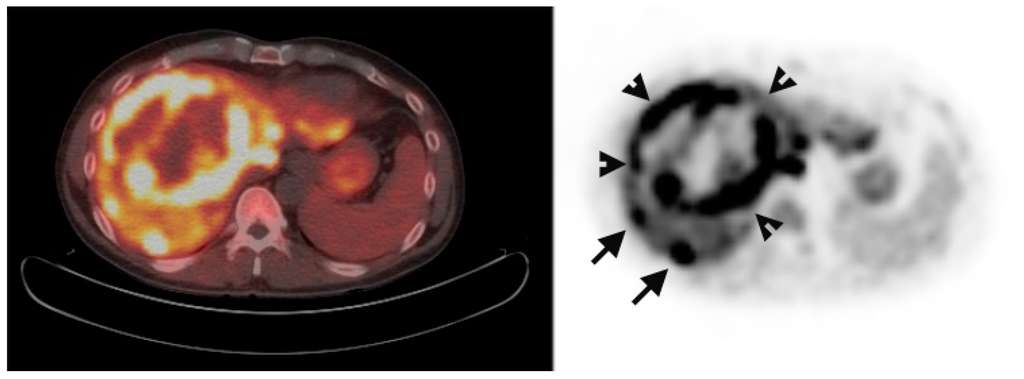

Multiple foci of increased FCh uptake in the liver consistent with multifocal or multinodular HCC (example, Figure 1) were noted in 8 of the 13 patients with increased primary tumor uptake. Of these, the areas of increased FCh uptake were adjacent to the treatment site (examples, Figure 2 and Figure 3) in 2 patients treated by local tumor ablation and 1 patient treated by liver resection. In one newly diagnosed case, PET demonstrated heterogeneous tumor FCh uptake with increased peripheral uptake and markedly diminished central uptake (Figure 4). Pathology in this case revealed a highly-necrotic tumor with Edmondson-Steiner grade 3 differentiation.

Multifocal recurrent hepatocellular carcinoma (HCC). Corresponding positron emission tomography (PET)/computed tomography (CT) (left) and PET (right) images demonstrate multiple foci of increased fluorocholine (FCh) uptake in the liver (arrows) ranging in diameter from 7 to 30 mm.

The first clinical study of FCh PET for detecting HCC was conducted by Talbot et al. [11]. Their initial study detected HCC in 12 of 12 patients who were imaged by FCh PET (8 newly diagnosed and 4 recurrent HCC) [11]. In 9 patients who also underwent conventional FDG PET imaging, only 5 of these patients had tumors detected on the basis of FDG uptake. A subsequent prospective study in 81 patients confirmed a superior rate of detection with FCh than with FDG, although data from this study also appears to suggest that FDG may have higher tumor specificity [16]. Like the current study, tumors smaller than 1 cm in diameter were detected with FCh PET/CT (Figure 1), which supports the potential for FCh PET to supplement existing radiographic criteria for making the non-histopathologic diagnosis of HCC.